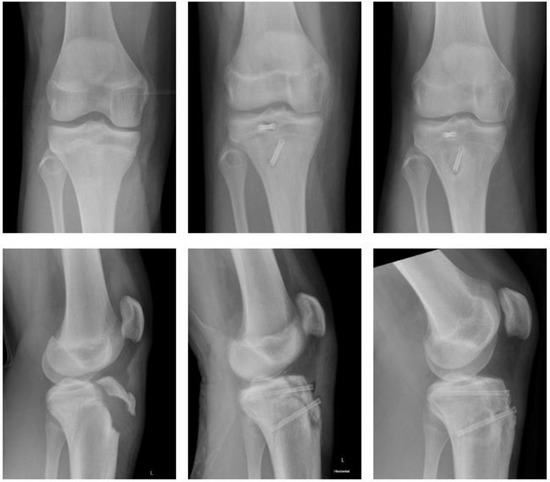

2.4.2. Fracture of the Medial Epicondyle

2.4.3. Fracture of the Lateral Condyle